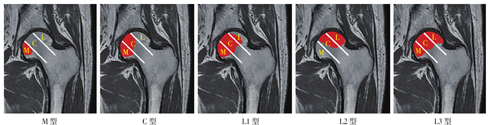

中国分型(中日友好医院分型)依坏死灶占据三柱情况进行分型:M型,坏死灶占据内侧柱;C型,坏死灶占据中央柱、内侧柱;L型,坏死灶占据全部三柱。依坏死灶占据外侧柱状态,外侧型又分为三种亚型:L1型,坏死灶占据部分外侧柱,尚有部分外侧柱存留;L2型,坏死灶占据全部外侧柱,部分占据中央柱,内侧柱未受累;L3型,坏死灶占据整个股骨头(图2[23]

图2 中国分型(中日友好医院分型)。依坏死灶占据三柱情况进行分型:M型,坏死灶占据内侧柱;C型,坏死灶占据中央柱、内侧柱;L型,坏死灶占据全部三柱。依坏死灶占据外侧柱状态又分为:L1型,坏死灶占据部分外侧柱,尚有部分外侧柱存留;L2型,坏死灶占据全部外侧柱,部分占据中央柱,内侧柱未受累;L3型,坏死灶占据整个股骨头。M,内侧柱;C,中央柱;L,外侧柱